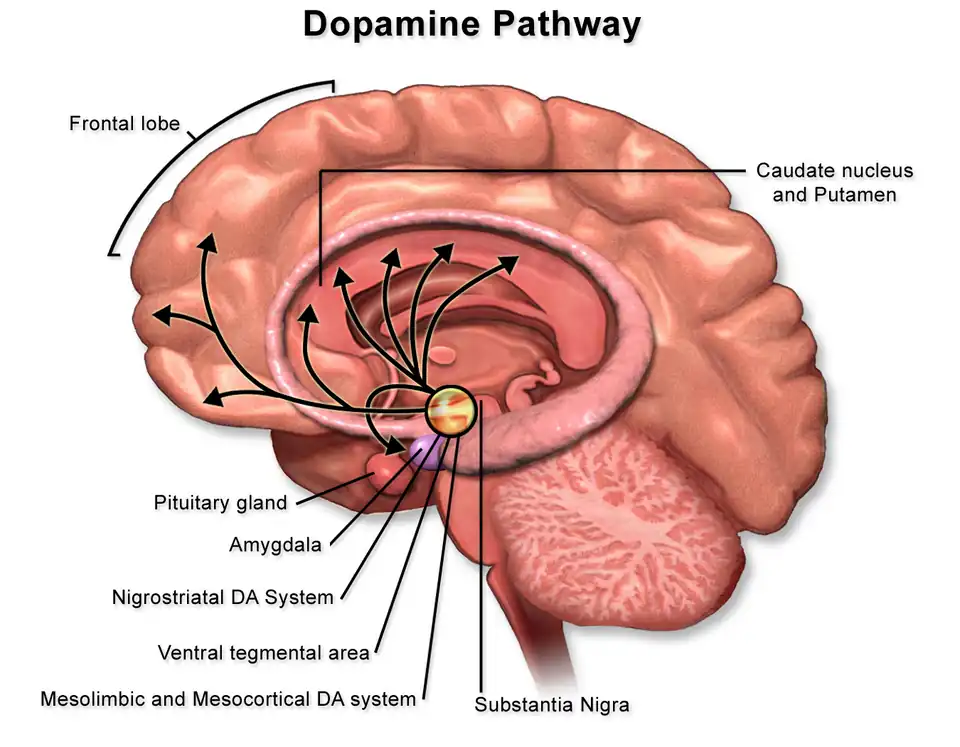

Mesolimbic pathway

The expectation of pleasure in behaviour results from the mesolimbic pathway; a system in which the neurotransmitter, dopamine is transported through the ventral tegmental area (VTA) to the nucleus accumbens and amygdala, areas heavily associated with the aspect of reward and mood (see Figure 2). The activation of this pathway occurs when a stimulus (i.e., food, drugs) is presented, resulting in the VTA signalling the release of dopamine into the nucleus accumbens. However, this process is not entirely fixed on natural rewards as research has shown the pathway to extend to 'higher-order pleasures' including music and social intimacy. This is noted in a neuroimaging meta-analysis conducted by Berridge and Kringelbach (2015) as it illustrated how several hedonic and secondary rewards exhibited immense overlap in their reward networks, elucidating to a shared system of neural coding and integration (Berridge & Kringelbach, 2015).

Moreover, pleasure perception is not limited to the reward pathway, as numerous structures have been shown to contribute to the experience of pleasure, namely the orbitofrontal cortex, insula, and anterior cingulate cortex (Berridge & Kringelbach, 2015).

Pleasure is experienced through the mesolimbic pathway, a process that transports the neurotransmitter, dopamine to the brain region, the nucleus accumbens. However, research has shown how this process is not exclusive to this pathway, as structures such as the orbitofrontal cortex, insula, and anterior cingulate cortex have illustrated activation and processing of the perception, coding, and activation of pleasure.